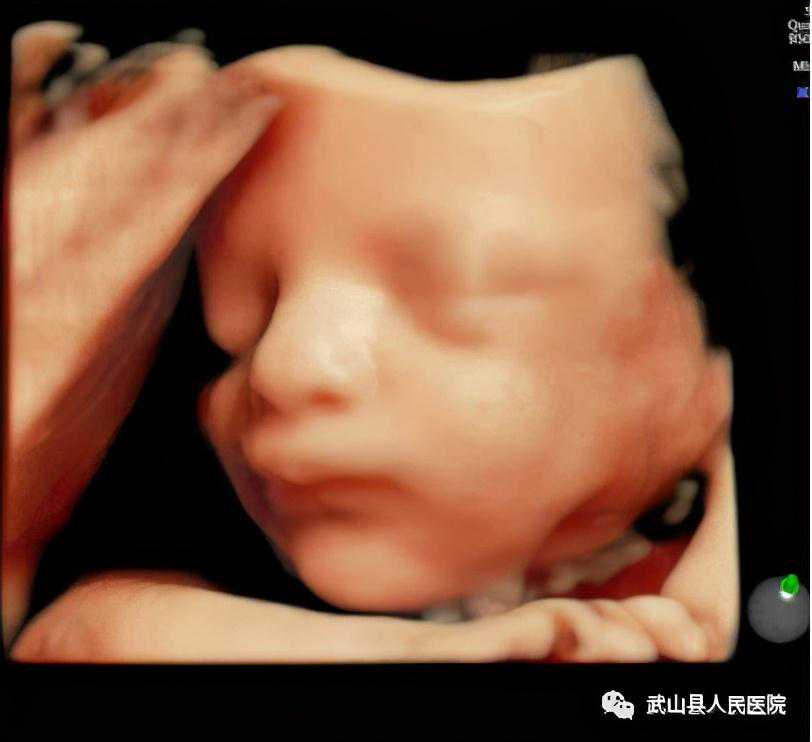

2.孕22周----24周,对胎儿主要解剖结构进行系统观察以及对严重结构畸形进行系统筛查。

武山县人民医院四维超声检查属Ⅱ级产前超声检查,主要针对卫生部规定的六大类严重结构畸形进行筛查,包括无脑儿、严重脑膨出、严重开放性脊柱裂、严重胸腹壁缺损内脏外翻、单腔心、致死性软骨发育不良。